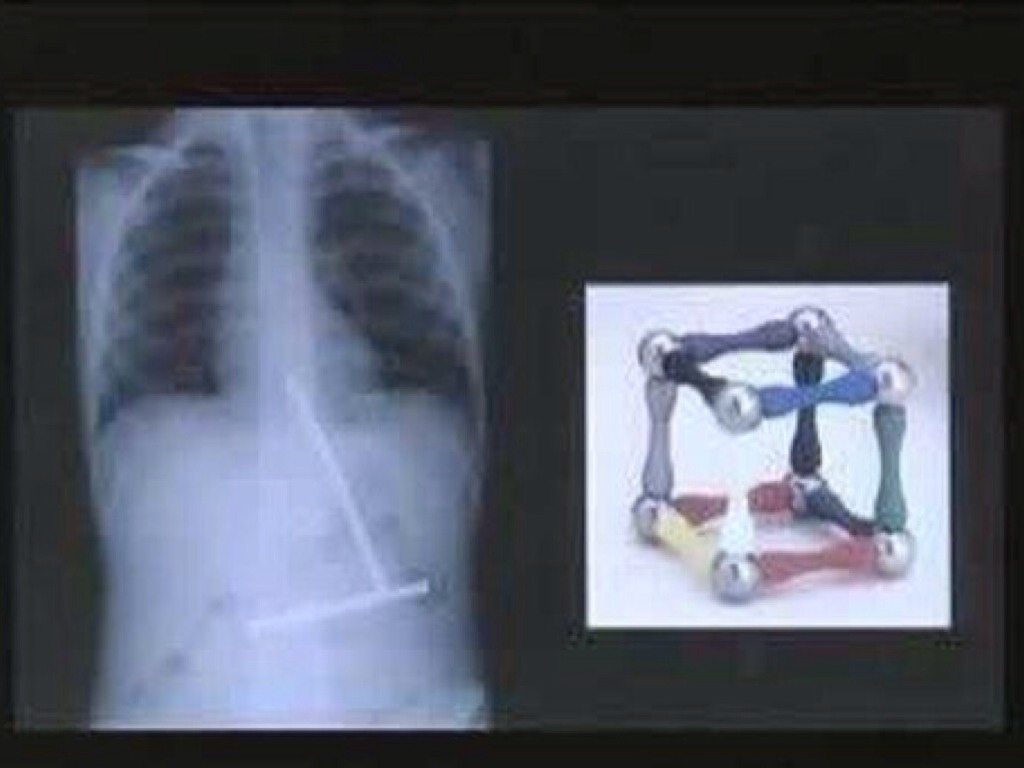

WHAT DID I SWALLOW?